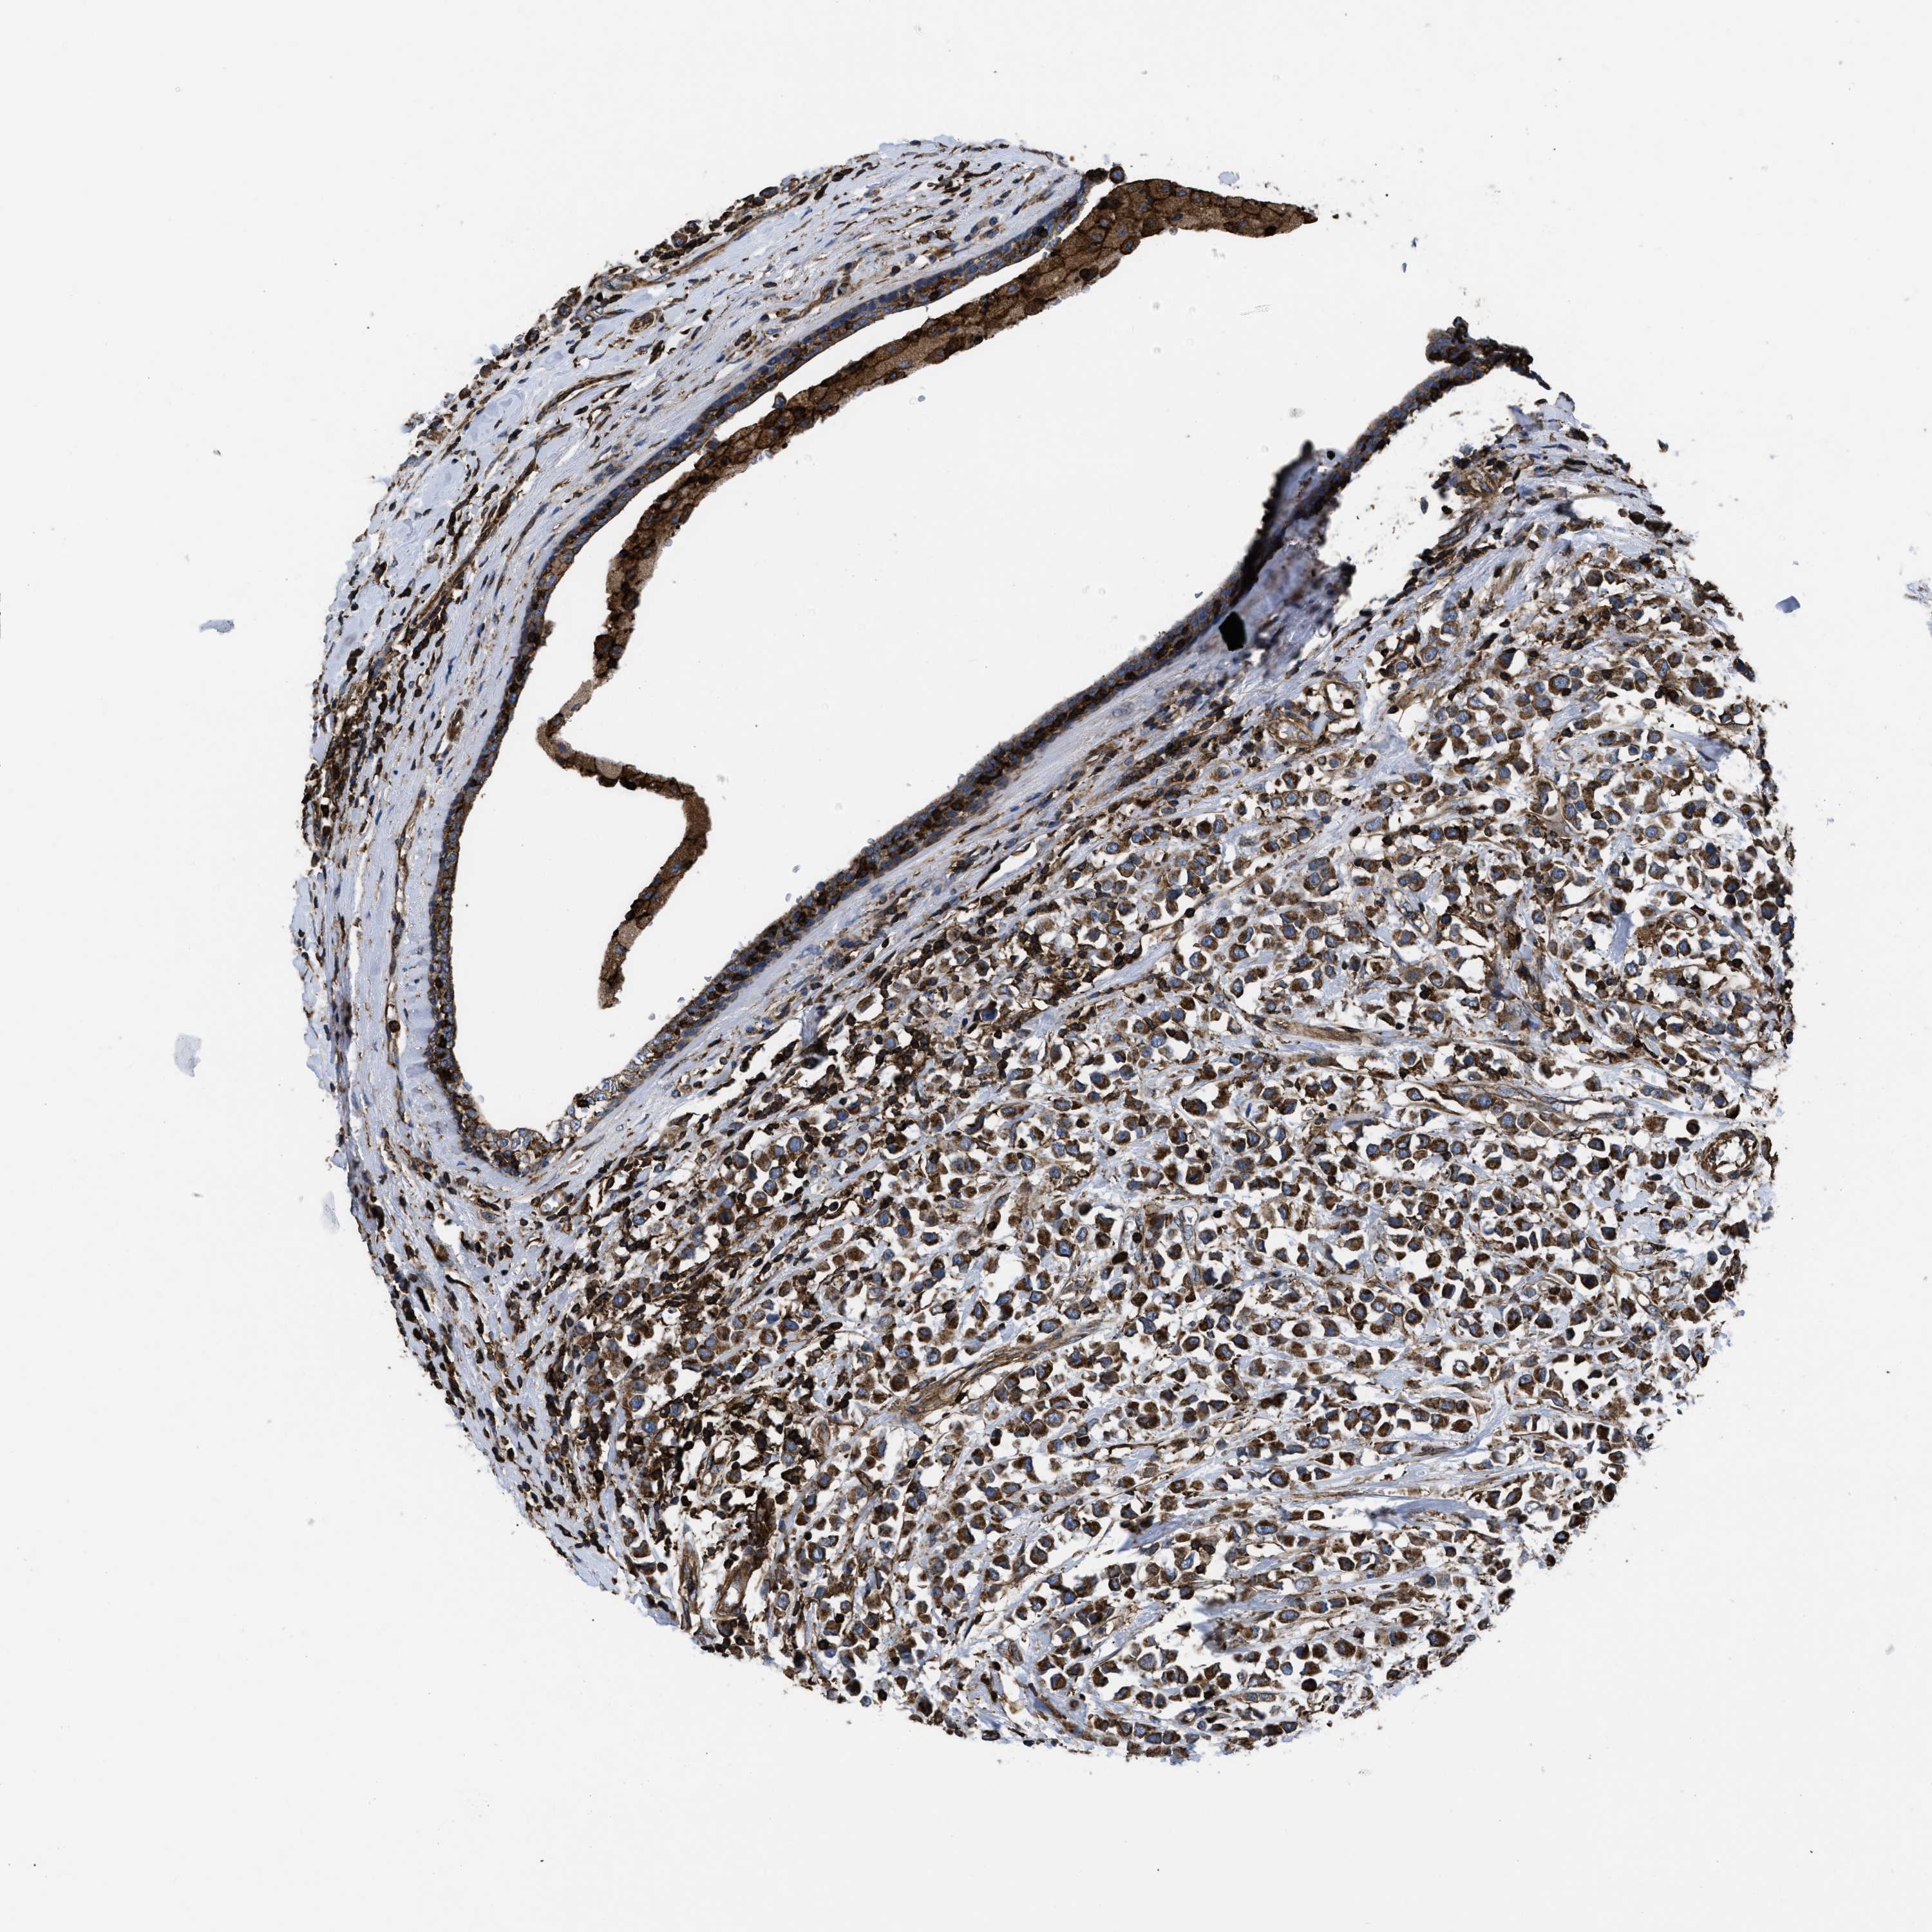

CANCER BREAST CANCER Show tissue menu

BRCA TCGA BRCA VALIDATION PROTEIN EXPRESSION